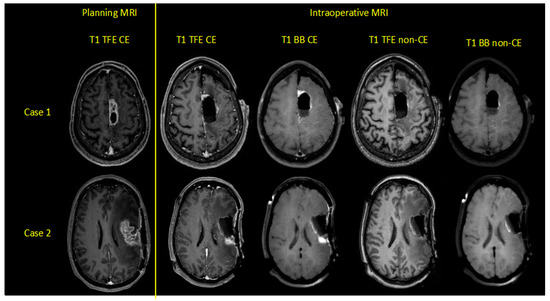

A flow chart with the categorization of each patient is provided in Figure 1. Exemplary cases with the investigated iMRI sequences are shown in Figure 2.

Figure 2. Exemplary cases of two patients harboring left-hemispheric glioblastoma multiforme, depicting contrast-enhanced (CE) and non-CE turbo field-echo (TFE) and Black Blood (BB) sequences for preoperative planning and intraoperative magnetic resonance imaging (iMRI).